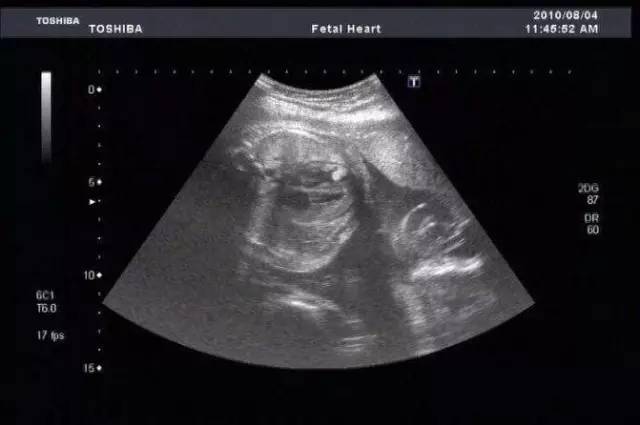

回到家,张霞不忍细问,带着女儿匆匆赶到医院。当看到女儿的B超检验结果,她更加不敢相信自己的眼睛——胎儿已经31周了。

“报案后给这个小孩做了引产手术,经过鉴定,胎儿的DNA和小女孩以及被告人的DNA有关联,小女孩和被告人是这个胎儿的生物学父母。”隋蔚说。